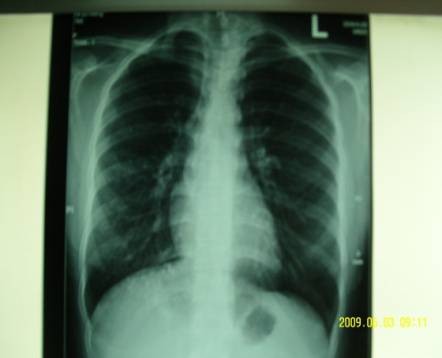

2009-05-26我女儿的病现在基本好了,我给他拍了胸片,有点支气管炎,原先的阴影基本消失,孩子已上学,十万分的感谢陶教授的救命之恩!

治疗后

按:急性重症肺炎中期、极期的肺部影像学特点绝大部分患者出现弥漫性肺部炎症异常表现。病变形态分为斑片状影,大片状影,斑片融合影像。病变密度为肺实变密度及磨玻璃密度影,肺纹理增粗模糊,肺实变的影像和临床表现相关联,持续高热时,肺部影像最为严重和广泛。此时西医治疗要点:要及时适量、足量使用糖皮质激素。中医辨证:疫毒犯肺,邪在气分。治则:清瘟泻热解毒,宣肺平喘。中西医结合治疗,短期内炎症吸收迅速,病情好转,没有遗留,邪去正安。